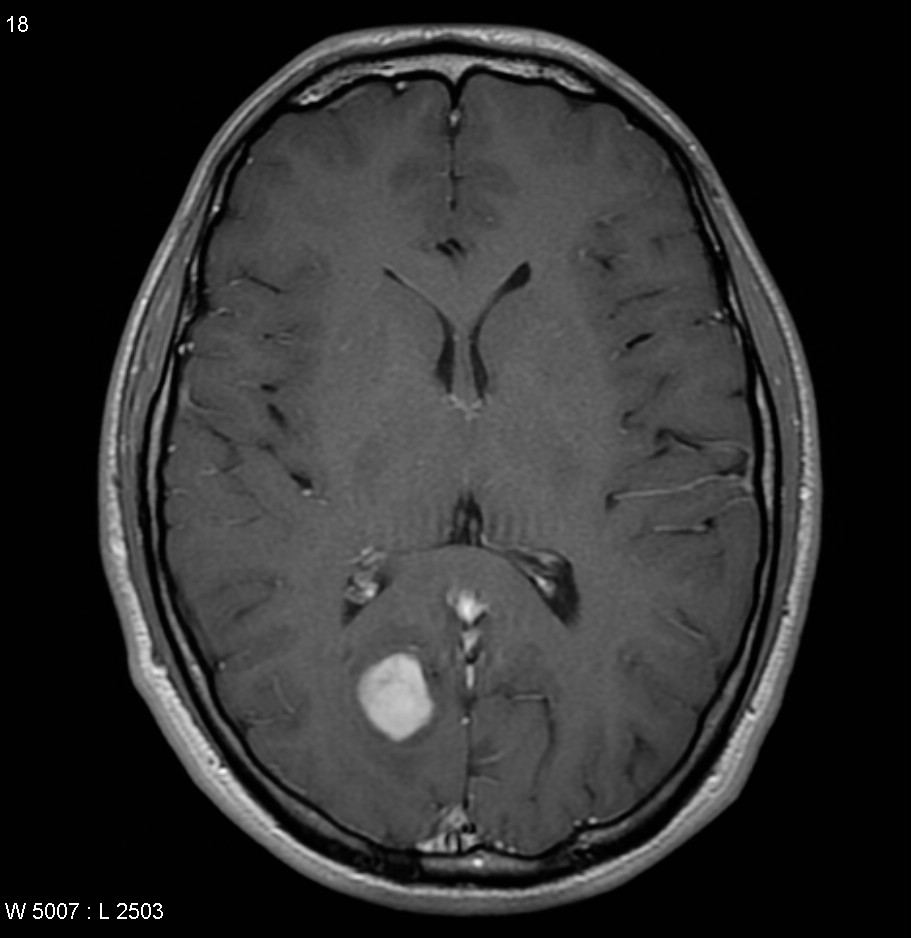

Patients with brain tumors may complain symptoms of headache, dizziness, vomiting, blurred vision, limbs weakness, etc.. Other symptoms include seizures and endocrine disorders; Personality or behavior changes may also occur. With modern advances in brain imaging technology, Computerized Tomography (CT) scan and magnetic resonance imaging (MRI) are the most commonly used diagnostic tools.

MRI does not involve radiation risk. Patients are required to lie inside the scanner with a strong magnetic field. Patients will not feel pain during the scanning process. MRI images can be achieved in a number of different angles and through a variety of different "signals", so as to letting us to explore more about the tumors’ nature, thus allowing neurosurgeons making the most appropriate treatment plan for patients.